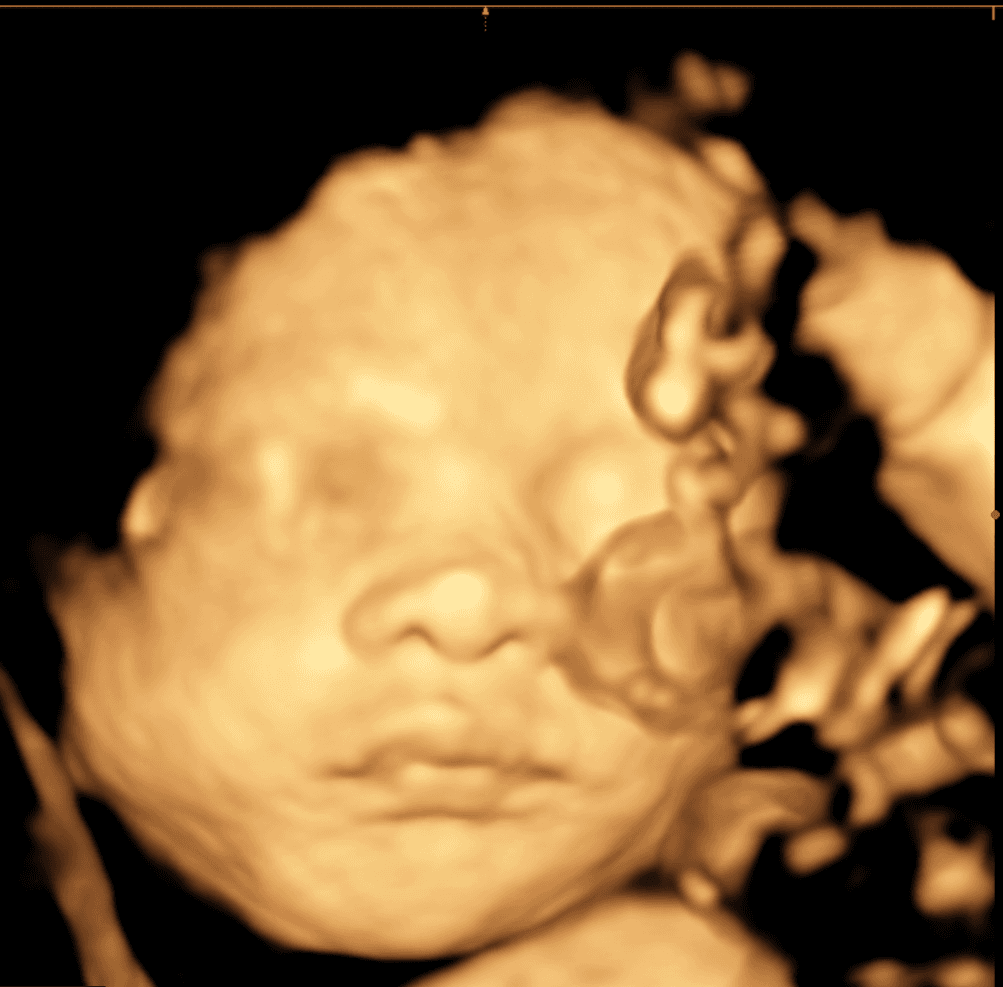

Explore our collection of ultrasound images and clinic photos. See the quality and clarity of our technology and the comfort of our facilities.

Book an appointment today and capture beautiful images of your baby. Our state-of-the-art technology provides clear, detailed ultrasound images for you to cherish forever.